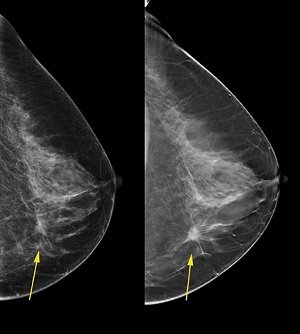

MAMMOGRAPHY in Breast Cancer

यह एक एक्सरे की जांच होती है. कुछ डॉक्टर आपको सोनोग्राफी को भेजकर कह सकते हैं कि यह भी मैमोग्राफी ही है. लेकिन सोनोग्राफी को सोनोमैमोग्राफी बोलते हैं.

और असली मैमोग्राफी एक्सरे जांच को ही बोलते हैं.

इस टेस्ट में आपके स्तन को एक्सरे मशीन में दो प्लेटों के बीच में दबाया जाता है. और एक्सरे लिया जाता है. आपके एक स्तन में गांठ है फिर भी अक्सर दोनों भी स्तन का एक्सरे किया जाता है.

इस जांच में कोई तकलीफ नहीं होती. हां आपको कुछ असहजता महसूस होती है. जांच की रिपोर्ट आपको तुरंत या शाम तक मिल सकती है.

इस जांच का खर्चा करीबन 2 से 3000 हो सकता है.

इस जांच में स्तन की गांठ को एक्स-रे के नजर से देखा जाता है. कहीं उस में कुछ कैंसर के लक्षण तो नहीं. अगर ऐसे कुछ लक्षण दिखाई देते हैं तो कैंसर की पॉसिबिलिटी की रिपोर्ट बनाई जाती है.